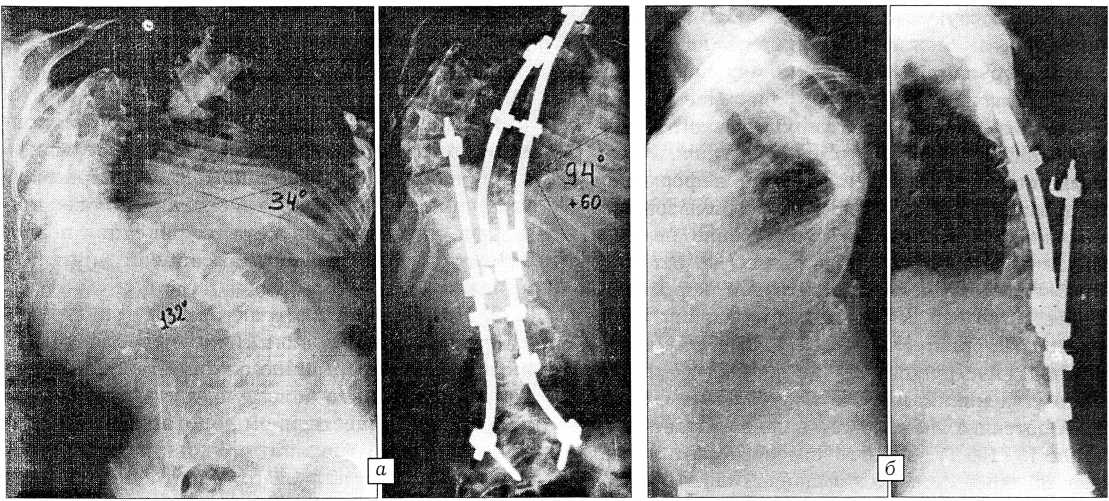

Использование системы CD позволило получить коррекцию общего угла в пределах 20-52° (табл. 4). Средняя коррекция составила 38,1° (рис. 2).

Рис. 2. Рентгенограммы больной Б. с диспластическим правосторонним грудным сколиозом III степени до операции и после коррекции деформации системой CD по стандартной методике. а — прямая проекция: до операции общий угол деформации 120°, после операции коррекция общего угла 38°; б — боковая проекция: до операции грудной кифоз несколько сглажен, после операции в пределах физиологической нормы; в — рентгенограммы реберного горба: после операции реберный горб уменьшился в результате достигнутой деротации.

Наименьшая коррекция — 20 и 25 была получена у 2 пациентов, которым ранее проводилось хирургическое лечение в других клиниках с использованием в одном случае дистрактора Харрингтона, в другом —конструкции Красноярской клиники. Результат оказался неудовлетворительным, и пациенты поступили в нашу клинику со сформировавшимся задним спондилодезом. Наибольшая коррекция (от 40 до 56°) отмечена у 9 больных с тяжелыми формами сколиоза (рис. 3).

Коррекция противодуги составила в среднем 27,2° (от 15 до 44°) и была наибольшей у тех больных, у которых соответственно отмечалась наибольшая коррекция основной дуги.

Важным представлялось также оценить деротирующий эффект при использовании системы CD. Из 11 больных, у которых была изучена торсия вершинного позвонка, у 7 выявлена деротация в 10°, у 4 деротации не отмечено. Рентгенологически доказанный деротирующий эффект клинически проявлялся уменьшением реберной деформации (см. рис. 2). Необходимость в торакопластике после коррекции деформации позвоночника отсутствовала у 5 пациентов (до операции реберный горб у них был слабо выражен).